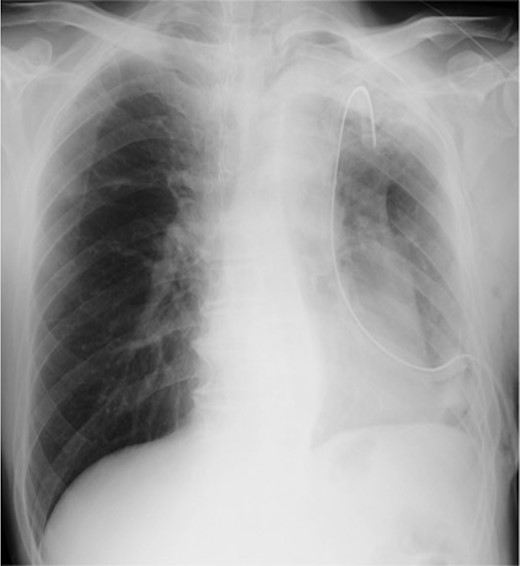

Chest X-ray image 2 h after the presence of bloody drainage from the thoracic tube caused suspicion of a left hemothorax.

Left lower lobectomy and lymph node dissection were performed. Preoperative computed tomography imaging revealed multiple bullae in the apex of the left lung and very thin bullae walls (Fig. 2A). Concerned that the patient would develop a second primary lung cancer or pneumothorax in the future, we simultaneously performed a bullectomy for two bullae with a lobectomy (Fig. 2B). Because the patient’s lung was highly emphysematous, linear staplers with PGA felt (Endo GIA™ Reinforced Reload with Tri-Staple™ Technology, cartridge color: purple, MEDTRONIC, Tokyo, Japan) were used for the bullectomy. We confirmed the absence of bleeding in the thoracic cavity and completed the operation (Video 1). The drainage from the thoracic tube turned bloody beginning 1 h after the operation. The drainage volume increased, and 600 ml of bodily drainage was observed for 2 h after the drainage had turned bloody. A chest X-ray imaging examination was performed, which confirmed fluid accumulation in the left thoracic cavity (Fig. 3). Because the patient’s anemia had also progressed, as compared with preoperative measurements (preoperative hemoglobin, 12.8 g/dl; 3-h postoperative hemoglobin, 9.1 g/dl), we determined that sustained bleeding had occurred in the thoracic cavity; we subsequently decided to carry out a reoperation to perform hemostasis. No air leakage was observed during the period between both operations.